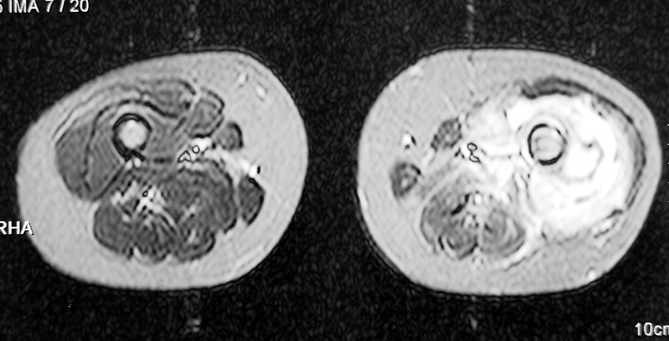

Kronik osteomiyelit, kemik ve yumuşak dokularda nekroza yol açar. Ölü kemik, patojen mikroorganizmalara ev sahipliği yapan bir nidus oluşturur. Konağın savunma sistemleri, mikroorganizmalarla baş etmek için sıklıkla optimal koşullarda değildir. Dolaşım bozukluğu yüzünden enfeksiyon bölgesine antibiyotikler yeterince ulaşamaz. Bu nedenle ölü dokuların ortamdan tamamen uzaklaştırılması gerekir (radikal debridman).

Vaka 3